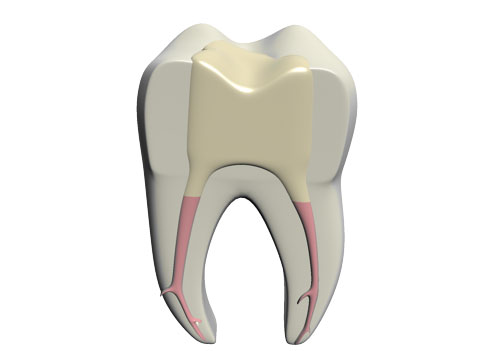

Der Begriff Endodont stammt aus dem Griechischen und bezeichnet das „Zahninnere“

Die Notwendigkeit einer endodontischen Therapie (Wurzelkanalbehandlung) ist dann gegeben, wenn sich die Pulpa entzündet oder abstirbt (Nekrose). Ursachen dafür sind häufig Karies, traumatische Verletzungen des Zahnes und undichte Restaurationen.

Durch das Eindringen von Bakterien in das Zahninnere wird das gesamte Kanalsystem des Zahnes infiziert. Die akute Phase der Entzündung läuft meist schmerzhaft ab. Weiterhin besteht die Möglichkeit, dass das Pulpengewebe schmerzfrei durch die Entzündung untergeht. Dabei können sich Bakterien ohne Gegenwehr des Immunsystems im inneren des Zahnes ausbreiten und den Kieferknochen entzünden. Wird die Entzündung nicht behandelt, entsteht an den Wurzelspitzen ein Abszess. Dieser wird von den Bakterien und ihren Endotoxinen (Botenstoffe) genährt und unterhalten.

Ziel der Wurzelkanalbehandlung ist es alle Bakterien und das infizierte Gewebe aus den Wurzelkanälen zu entfernen, das Wurzelkanalsystem zu desinfizieren und zuletzt bakteriendicht zu verschließen.